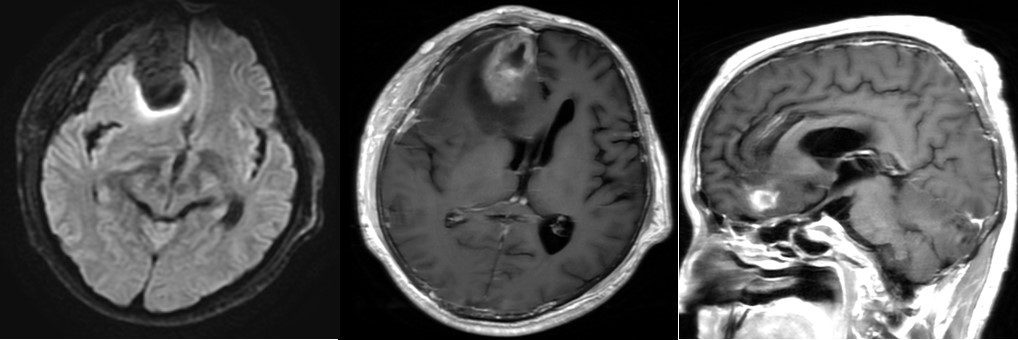

病例2 男,45y,胶质瘤术后3天

胶质瘤术后复查的检查,在临床中再常见不过,常规扫描方案头颅平扫+增强,目前只有部分医院会结合其他技术,例如灌注去综合评估患者术后情况。这次我们遇到了一例胶质瘤术后患者,申请单为头颅平扫+增强,图像如下:

T1上右侧额叶高信号,提示有出血,增强病灶强化,肿瘤未切除干净?

增强反映的是血脑屏障是否完整,患者做了手术,血脑屏障肯定是被破坏了,这时无法分辨是残余的肿瘤强化还是术后损伤。灌注可能给出答案,灌注反映的是组织的微血管分布和灌注情况,若有残余的肿瘤,则表现为灌注升高,正好我们在增强前做了不打药灌注3D ASL: